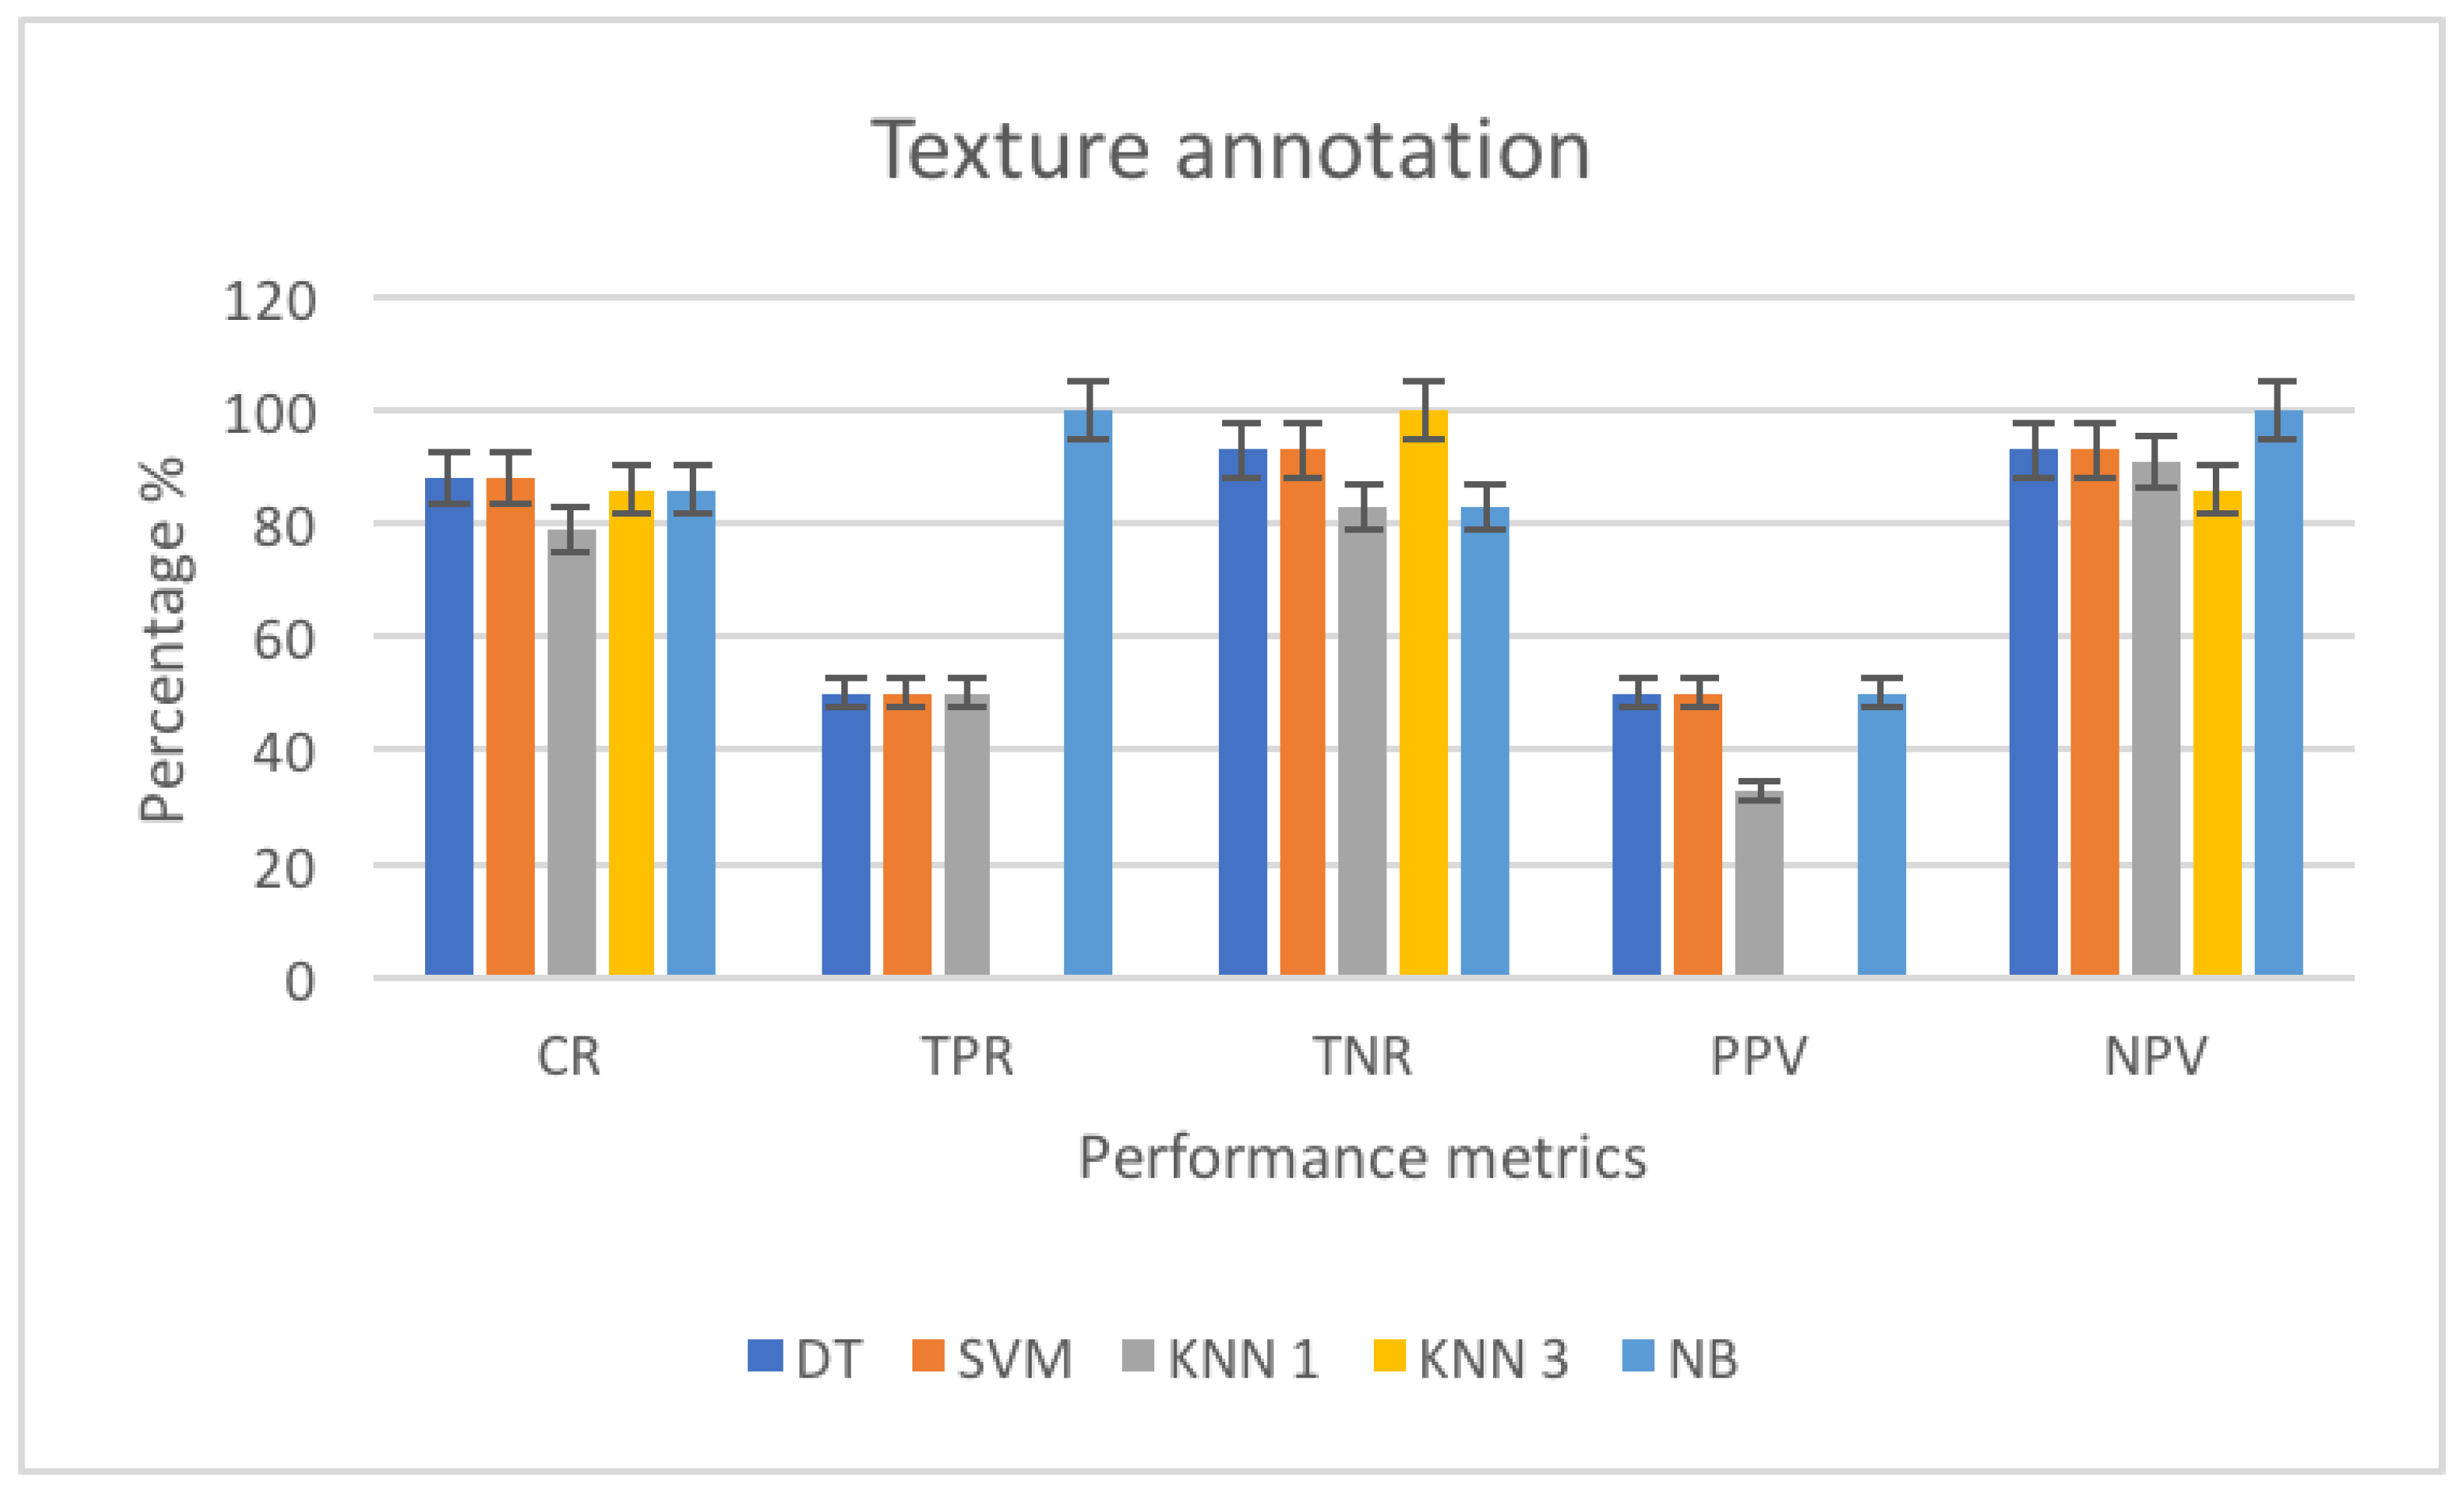

3.4.2. Texture Annotation